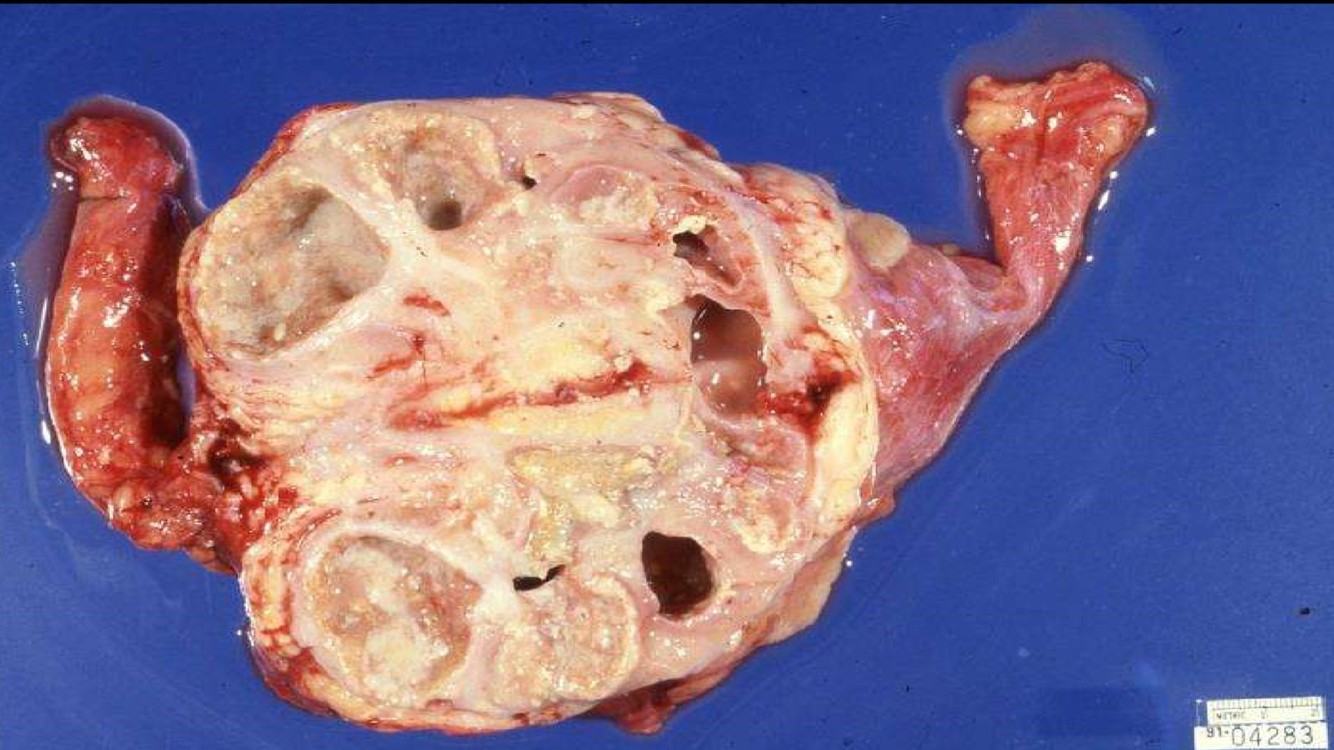

XANTHOGRANULOMATOUS PYELONEPHRITIS

- Often associated with large staghorn calculi of renal pelvis

- Many of these patients may have UTI, secondary to E. coli or Proteus

- May presents as a mass-like lesion